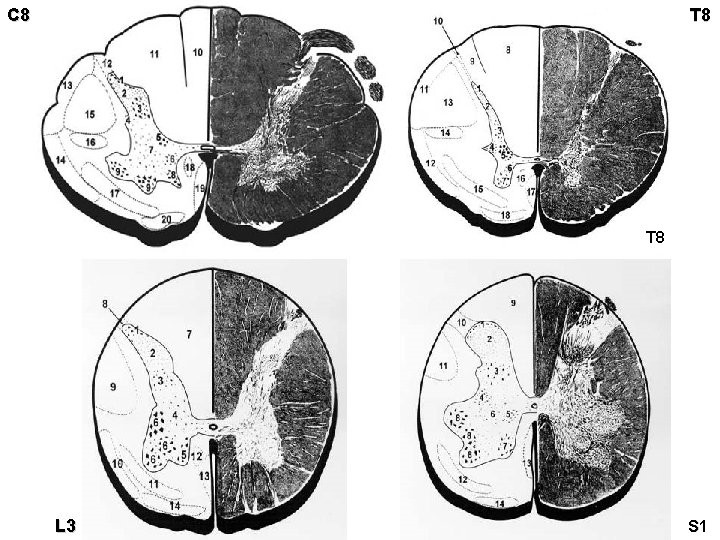

C 8 T 8 L 3 S 1

Mícha – vnitřní stavba obecné zásady • podélné uspořádání – vlákna = provazce = bílá hmota – shluky buněk = jádra = šedá hmota • příčné uspořádání – aferentní & eferentní vlákna – křížení • komisurální (spojková) • dekusační (zkřížená) • somatotopické uspořádání

Laminae spinales Rexedi I-X I = nucleus marginalis (apex cornus posterioris) II = substantia gelatinosa Rolandi (caput c. p. ) III+IV = nucleus proprius (cervix c. p. ) V = cervix c. p. VI = basis c. p VII = cornu laterale – ncl. thoracicus posterior Stilling-Clarke – ncl. intermediolateralis – ncl. intermediomedialis VIII+IX = cornu anterius – ncl. anterolateralis, anteromedialis, posteromedialis, posterolateralis, centralis X = commissura grisea ant. + post.

Somatotopické uspořádání